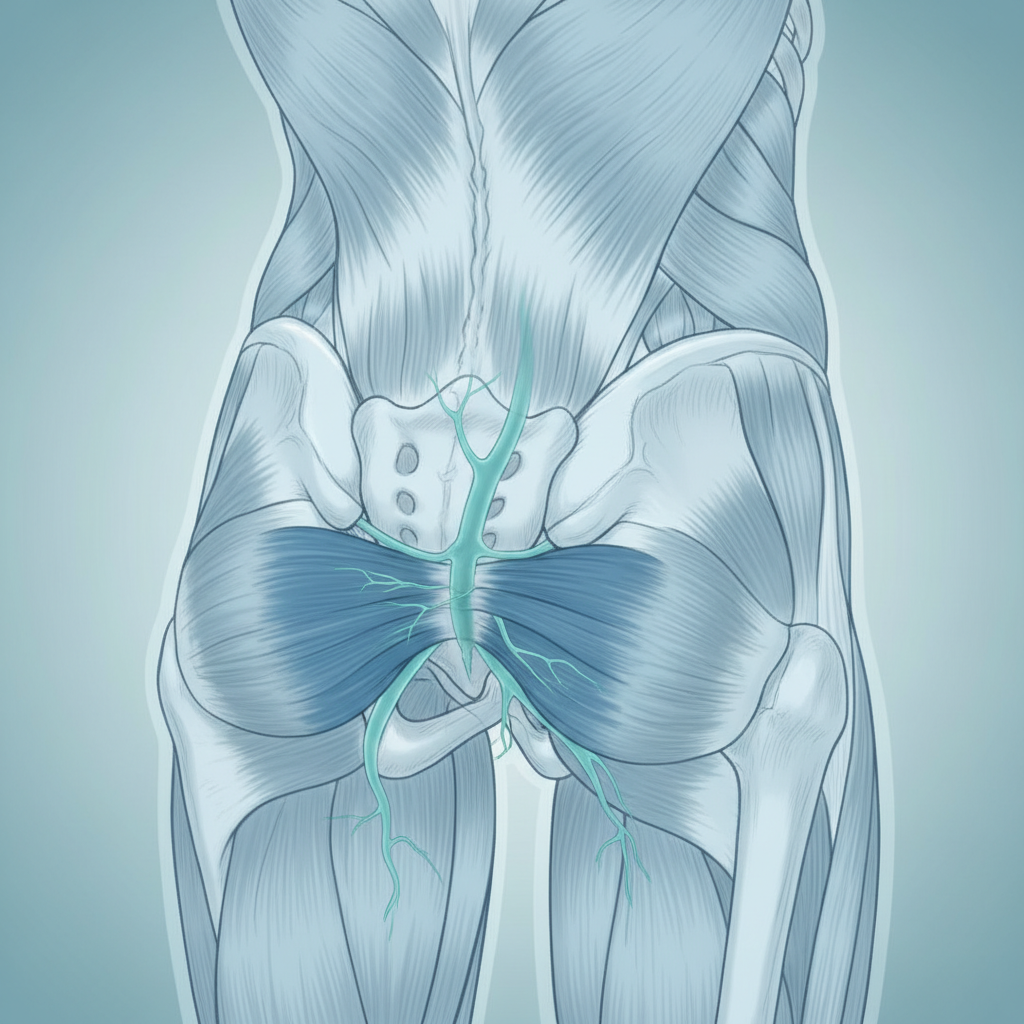

También son referencia en suelo pélvico (unidades especializadas para mujer y hombre) y en readaptación oncológica y cardiopulmonar — áreas que están fuera de mi especialidad. Si un paciente de AGM necesita trabajo de control motor intensivo o rehabilitación post-operatoria con gimnasio, ADH es mi primera derivación.

| Suelo pélvico, readaptación oncológica o cardiopulmonar | ADH Clínica |